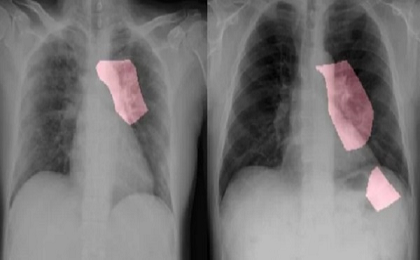

Hầu như cả thế giới đang chiến đấu với một kẻ thù chung là đại dịch COVID-19. Căn bệnh tàn khốc này đang lan rộng bất chấp biên giới, quốc gia. Bệnh chưa có thuốc chữa. Các nhà khoa học từ Đại học Copenhagen đã bắt đầu sử dụng trí trí tuệ nhân tạo để dự đoán bệnh nhân corona.